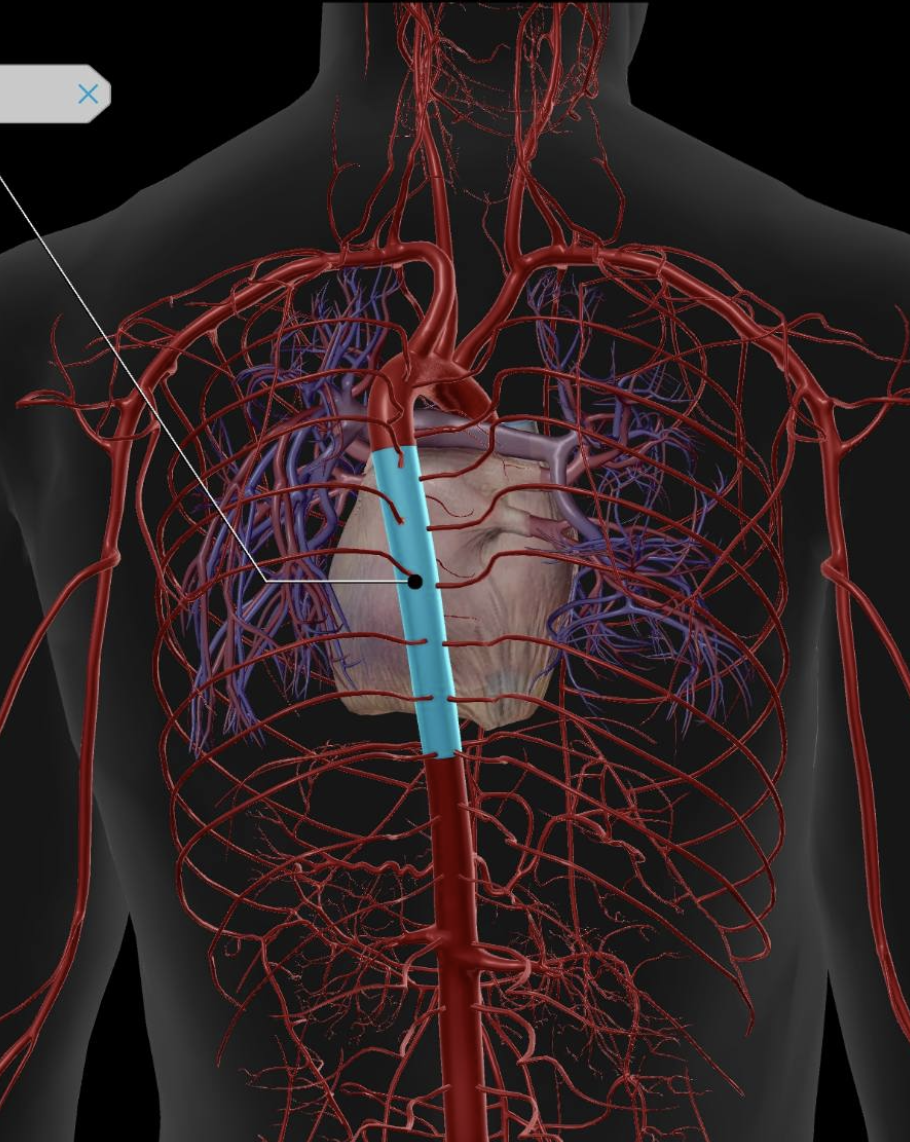

Abdominal Aorta

Thoracic Aorta

Inferior Vena Cava